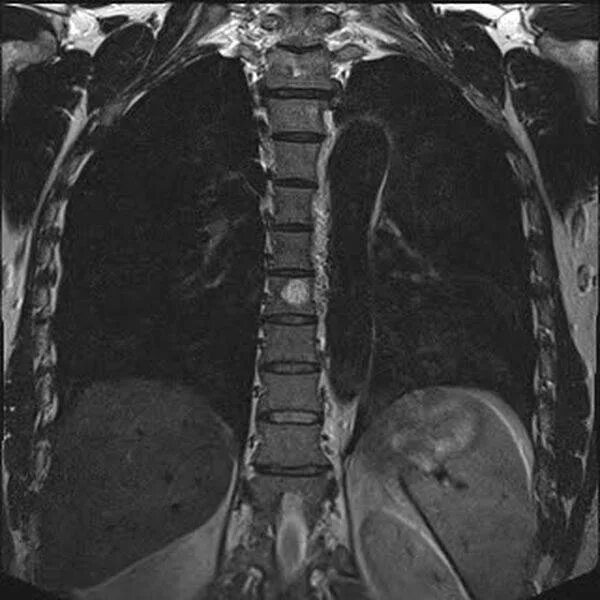

Метастазы в крестце